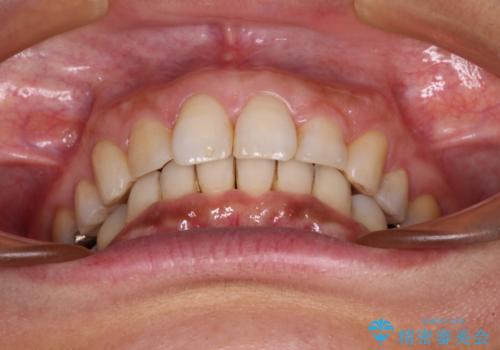

- 以前行った抜歯矯正が後戻りし、開いてしまったスペースが気になるとのことで来院された患者様です。

インビザラインを用いて開いてしまったスペースと前歯のデコボコを改善することとしました。

矯正治療後には気になっていた銀歯をセラミッククラウンやセラミックインレーにて治療することとしました。

上顎前歯を左右対称となるように歯列を整えたいとのことでしたが、すり減って形態が大きく異なっていたため、できる範囲での仕上がりとなりました。